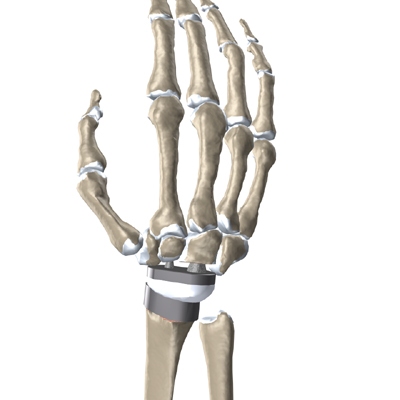

The Artificial Wrist

Some early artificial wrist joints were made entirely of flexible silicon plastic. These plastic joints were used primarily as spacers to keep the joint surfaces from rubbing together.

Modern artificial wrist joints are made of metal and plastic. The part that fits against the end of the radius bone of the forearm is called the radial component. It is made up of two pieces. A flat metal piece is placed on the front part of the radius. It has a stem that attaches down into the canal of the bone. A plastic cup fits onto the metal piece, forming a socket for the artificial wrist joint.

The part that replaces the small wrist bones is called the distal component. This piece is made completely of metal. It is globe shaped to fit into the plastic socket on the end of the radius. The metal distal component is attached by two metal stems that fit into the hollow bone marrow cavities of the carpal and metacarpal bones of the hand.

The plastic used in artificial joints is tough and slick. It allows the two pieces of the new joint to glide easily against each other as you move your wrist. The ball and socket allow movement of the wrist in all directions.